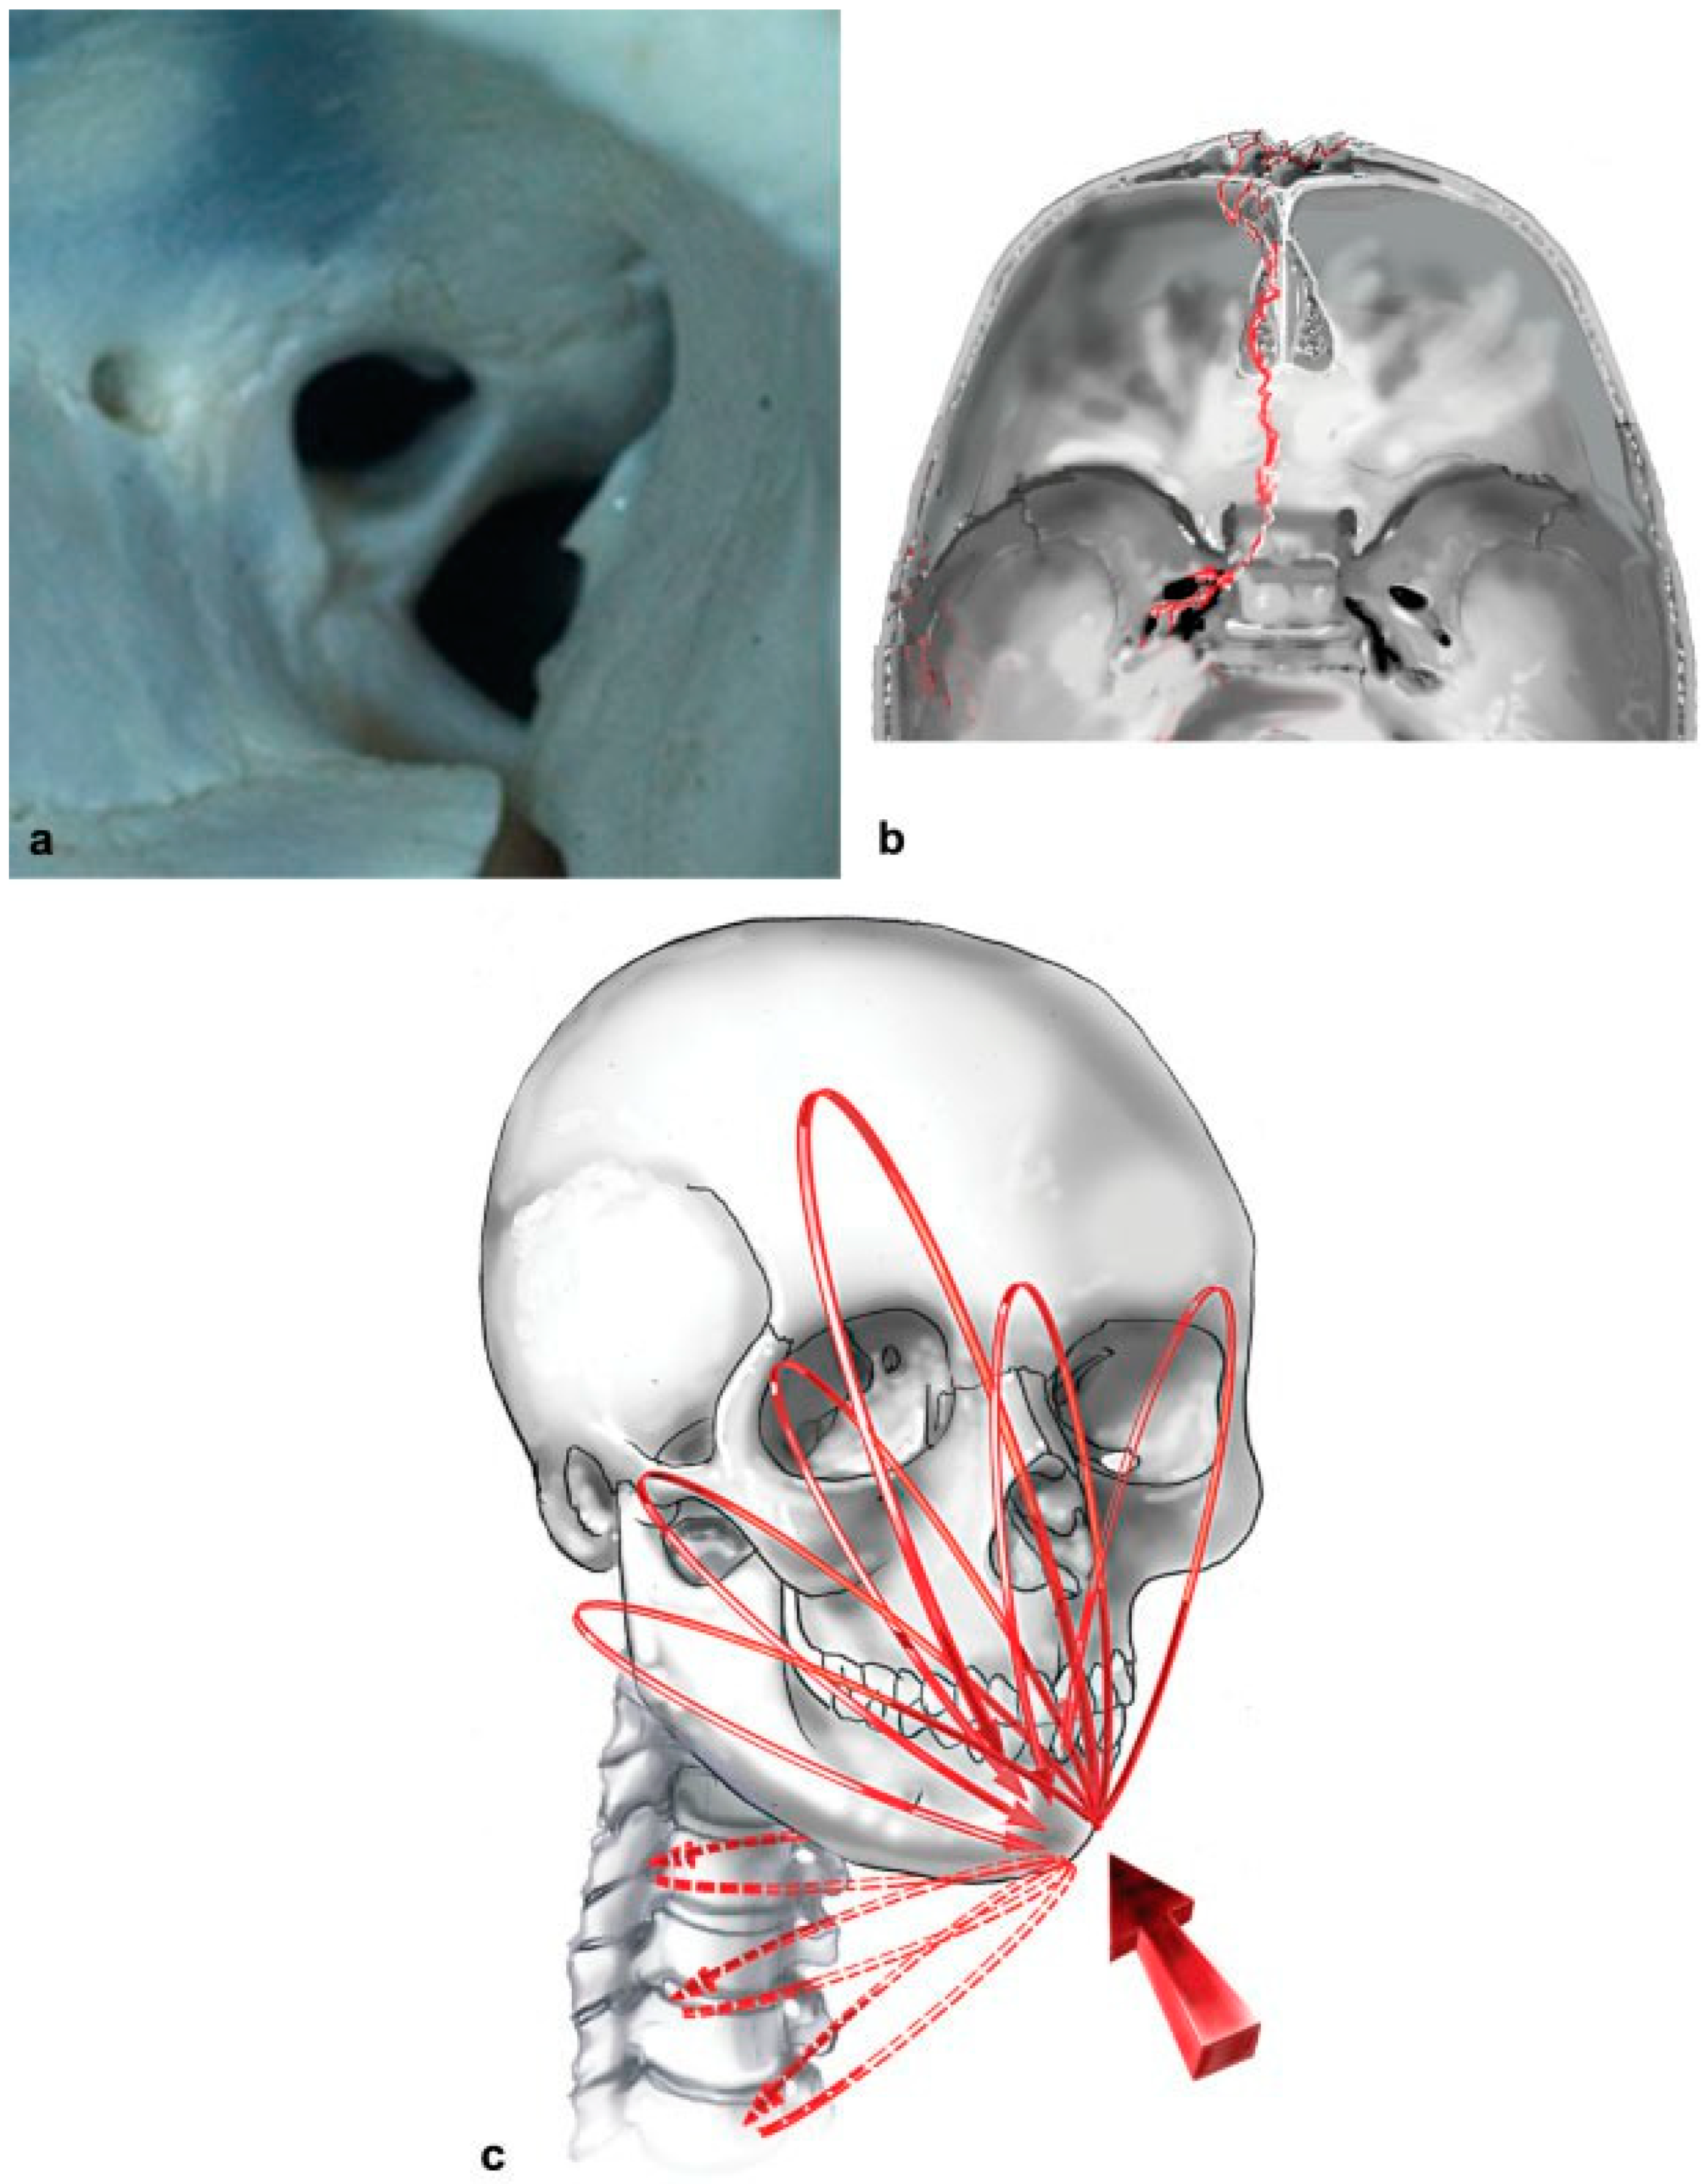

3. “The orbital floor … is formed in greater part by the orbital plate of the maxilla, … and completed anterolaterally by part of the orbital surface of the zygoma and posteriorly by a small triangular area (the processus orbitalis) of the palatine bone.” Whitnall (1921).

The three bones in the floor of the apex are often preserved after high-velocity impact, even when the orbital frame and bilge of the floor of the orbit are disrupted. Preserved apical floor provides structure upon which a split cranial bone graft may rest and is referred to as the “posterior ledge”[34] and the “pre-annular shelf”[33,40] (Figure 19a). Most basilar and frontobasilar fracture lines traverse the roof of the ethmoid, then deviate laterally upon reaching the roof of the sphenoid sinus, to end at the carotid canal or the foramen ovale, lacerum, or spinosum [44] (Figure 19b). Even with such extreme skullbase injury,[43,45,46,47,48] the pre-annular shelf (in the floor of the apex) skirts injury and is consistently available (in a survivor cohort) [48] as a stable platform to facilitate pan-orbital repair.

Rudderman et al. have demonstrated distribution of facial force equilibrium circuits (FFEC) to and from the cranium[49] and, we have speculated the presence of circuits to and from “the microbuttresses of the apex of the orbit, posterior skull base (occiput), and the vertebrae of the upper cervical spine” following impact (Figure 19c),[50] even though the shelf in the surviving cohort is most often spared fracture, upon frontal impact.

Figure 19. (a) The pre-annular shelf in the posterior floor of the orbit is most often preserved despite high-impact injury; the shelf varies in size and bone density and is the key for pan-orbital repair, photograph copyright Richard A. Pollock and Thieme Medical Publishers, Inc. (b) Art depicting the classic location of a frontobasilar fracture skirting the pre-annular shelf of the apical floor to terminate in one of several skull-base foramina, illustrated by Bill Winn, copyright Richard A. Pollock and Thieme Medical Publishers, Inc. (c) Facial force equilibrium circuits (FFEC) according to Rudderman, Mullen, and Phillips and speculated extension of circuits to orbital apex, occiput, and vertebrae of the upper cervical spine,26 illustrated by Bill Winn, copyright Randal H. Rudderman, Robert L. Mullen, John H. Phillips and Thieme Medical Publishers, Inc.